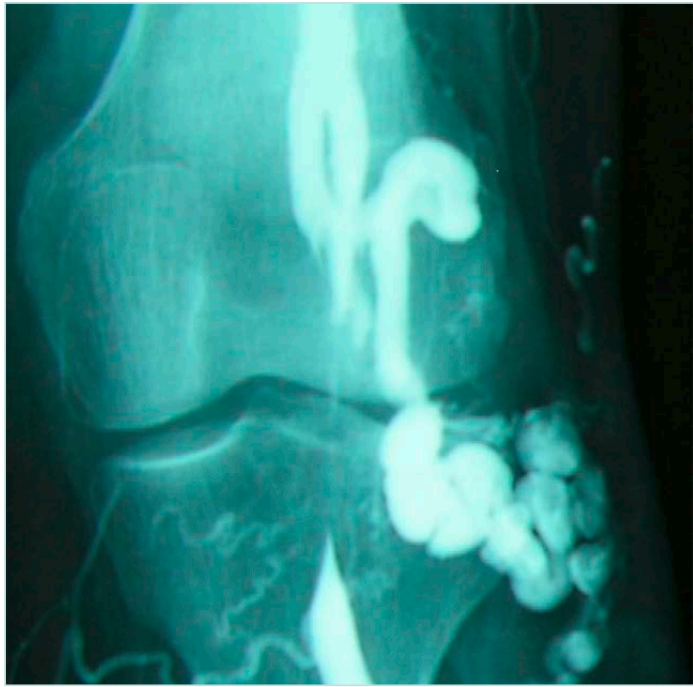

Our reference test remains dynamic phlebography.2 The examination is performed on a tilting table at 60° angle, with 3 manual injections of contrast agent: in neutral, foot extension, and foot flexion positions.

The surgeon should be in the room during the phlebography, for better evaluation of the anatomical pattern of the compression and to ask for more incidences as needed. In recurring varicose veins after small saphenous ablation, the surgeon can map the tributaries and perforators, which act as a spontaneous bypass over the compression (Figure 4 shows ascending phlebography: vein compression in the 3 positions of the foot; Figures 5 and 6 show ascending phlebography: spontaneous bypass of a venous popliteal compression).